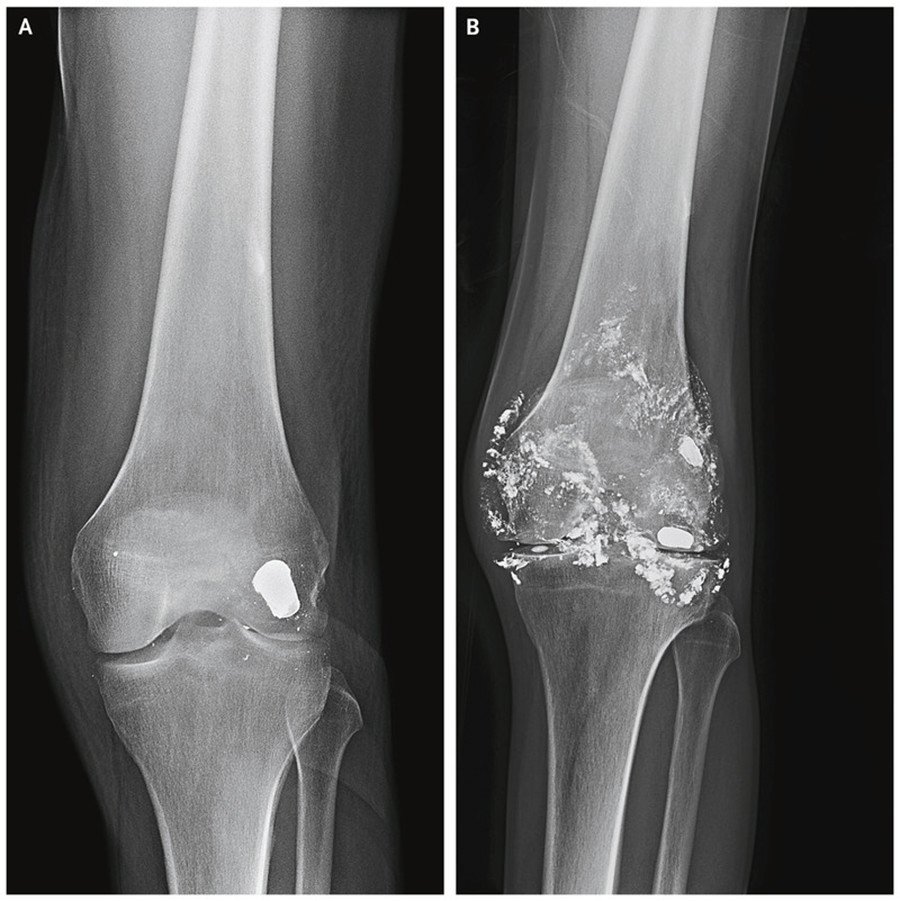

Este inusual caso clínico fue dado a conocer este jueves en la Revista The New England Journal of Medicine. Según se explica, el paciente fue víctima de un disparo en una rodilla catorce años atrás. Las radiografías revelaron que el proyectil quedó encajado en la parte posterior de su fémur, cerca de la articulación de la rodilla y nunca fue retirado.

Con el paso del tiempo, la bala fue desintegrándose en pequeños fragmentos que entraron en el tejido que recubre la rótula, alrededor de toda la articulación y en el líquido sinovial. Los estudios de laboratorio detectaron una anemia microcítica (glóbulos rojos más pequeños y con menos hemoglobina) y un elevado nivel de plomo, pero sin otros síntomas de intoxicación.